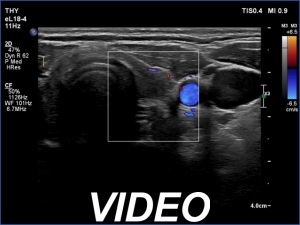

First examination (first row of images):

Ultrasonography. The thyroid was minimally hypoechoic. There was a small, discrete lesion in the upper pole of the right lobe. The left lobe had a larger and several tiny hypoechogenic lesions. The large lesion presented partly blurred, partly lobulated margins.

Cytology was performed from the large hypoechoic lesion in the left lobe and resulted in subacute, de Quervain's thyroiditis.